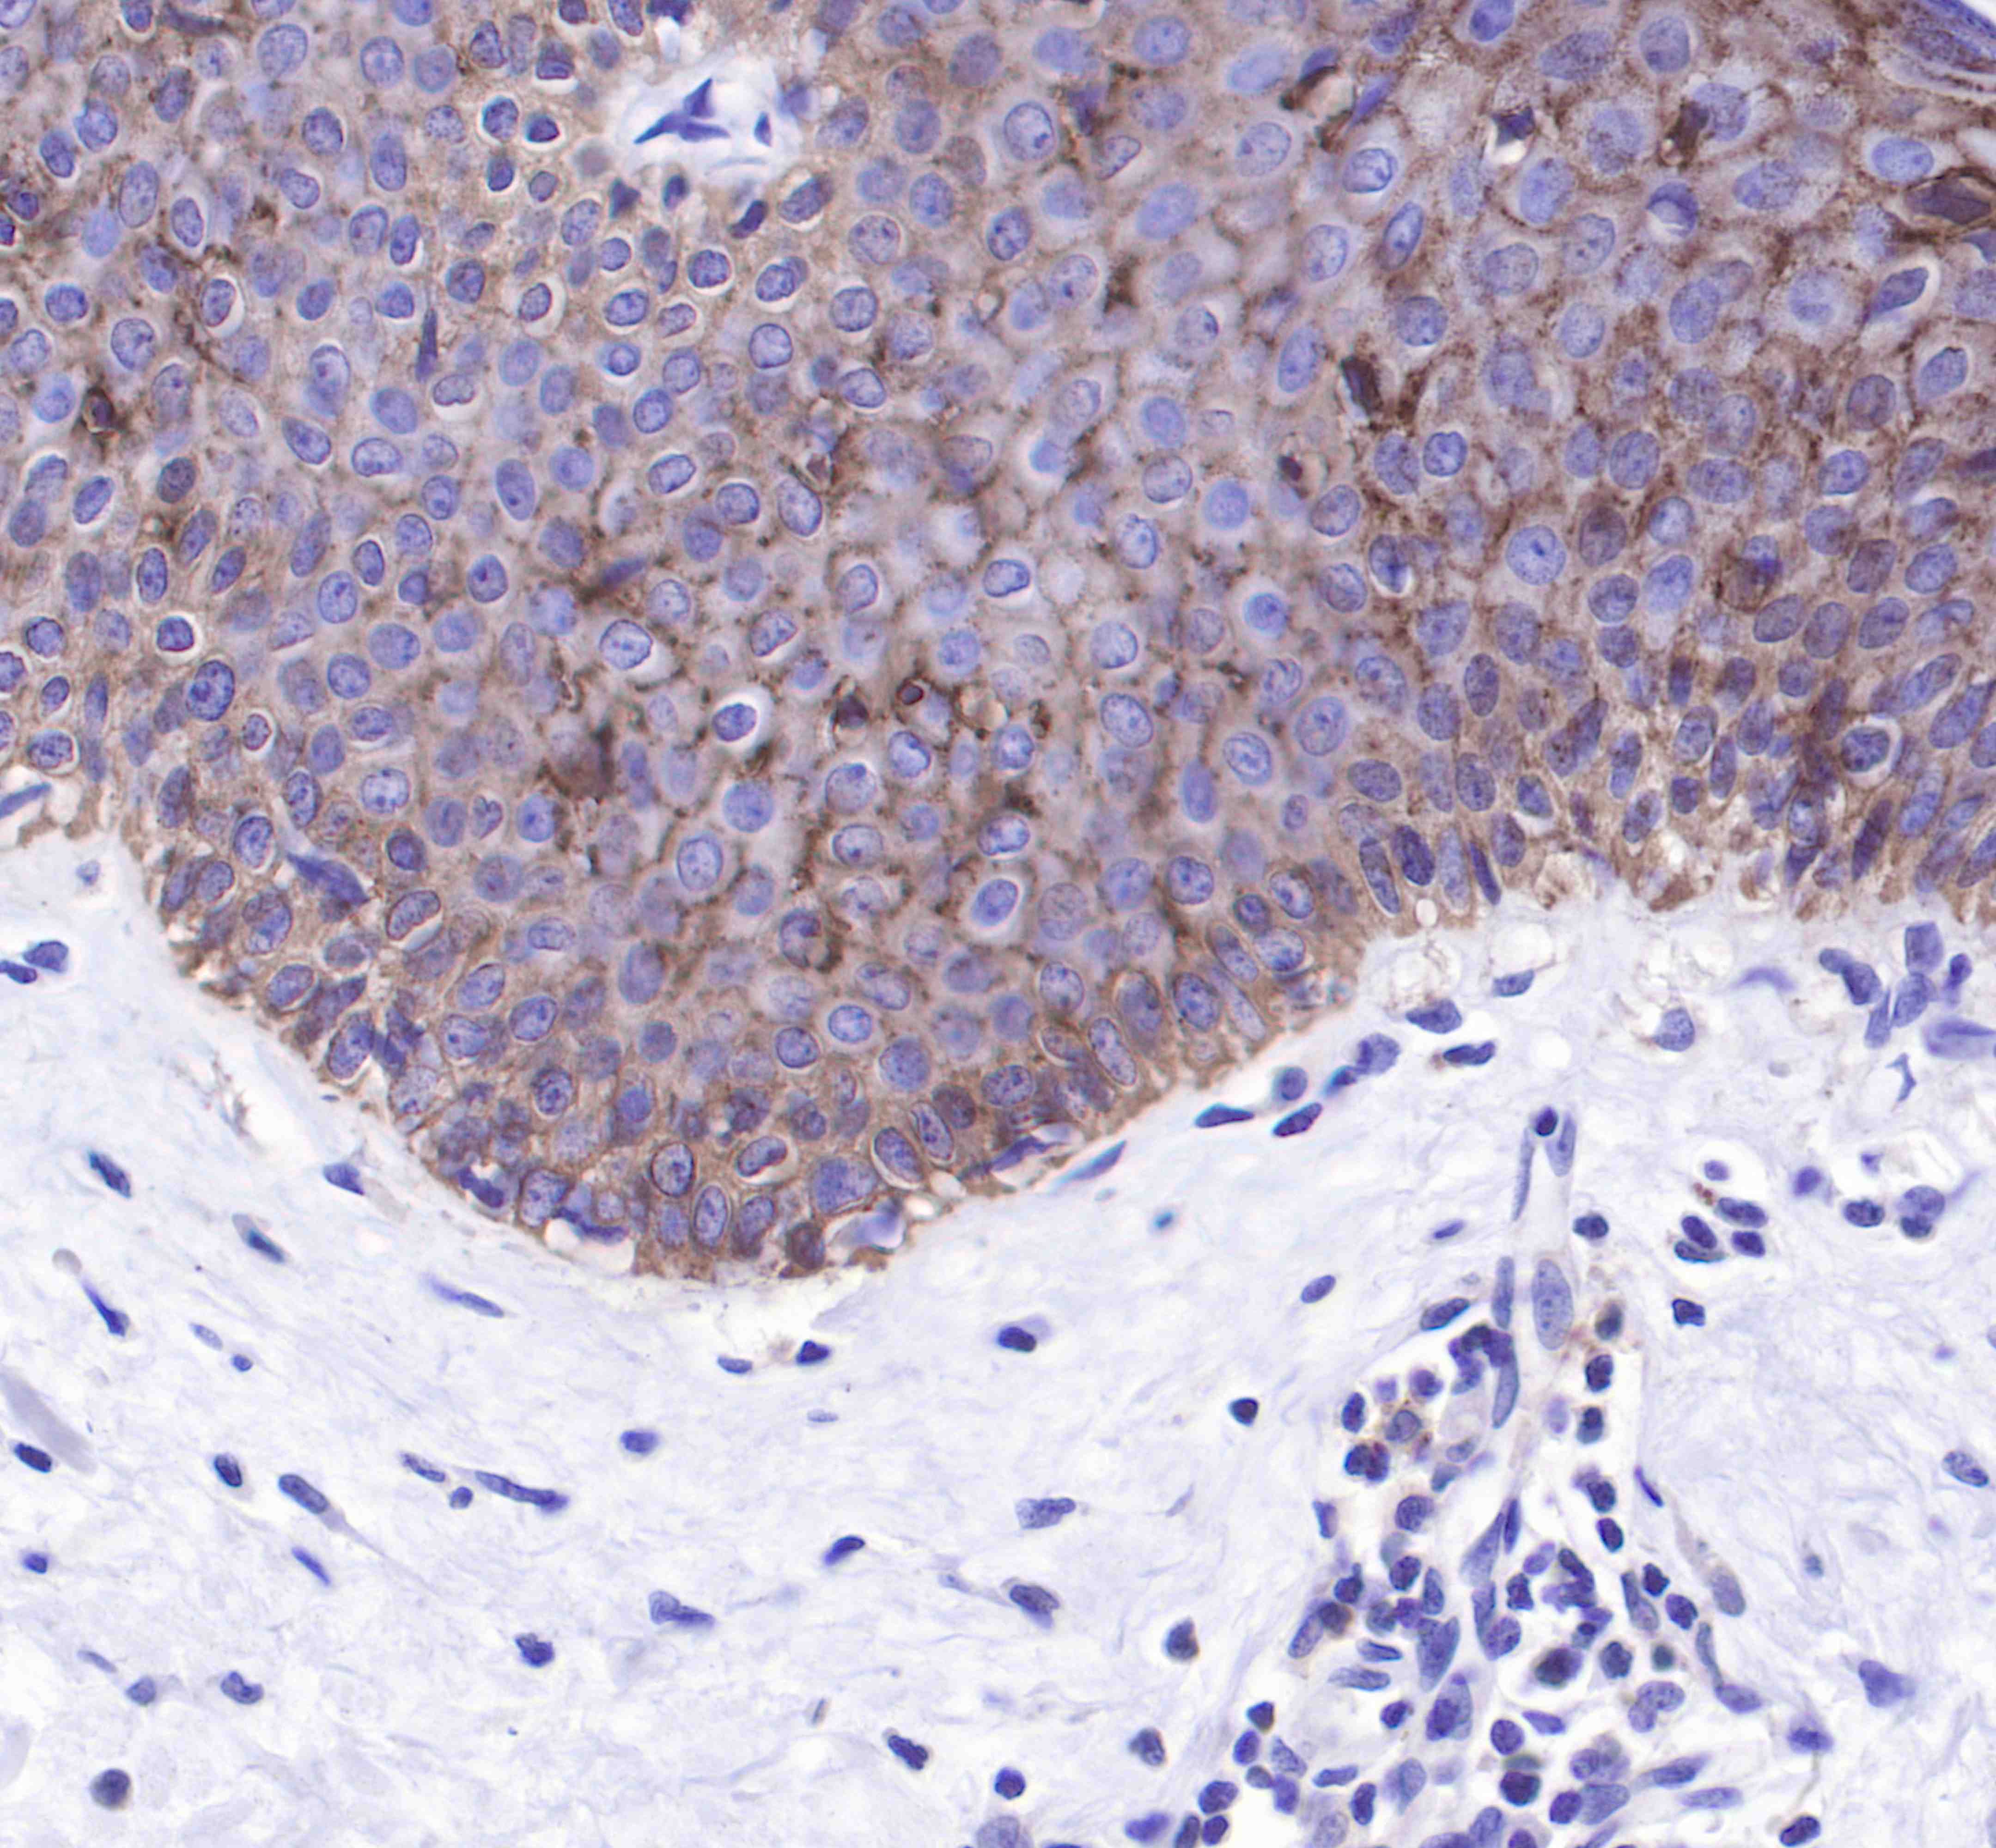

| IHC-P |

1:250 |

Claudin-1 is a protein that in humans is encoded by the CLDN1 gene.It belongs to the group of claudins.

Tight junctions represent one mode of cell-to-cell adhesion in epithelial or endothelial cell sheets, forming continuous seals around cells and serving as a physical barrier to prevent solutes and water from passing freely through the paracellular space. These junctions are composed of sets of continuous networking strands in the outwardly facing cytoplasmic leaflet, with complementary grooves in the inwardly facing extracytoplasmic leaflet. The protein encoded by this gene, a member of the claudin family, is an integral membrane protein and a component of tight junction strands. Loss of function mutations result in neonatal ichthyosis-sclerosing cholangitis syndrome.